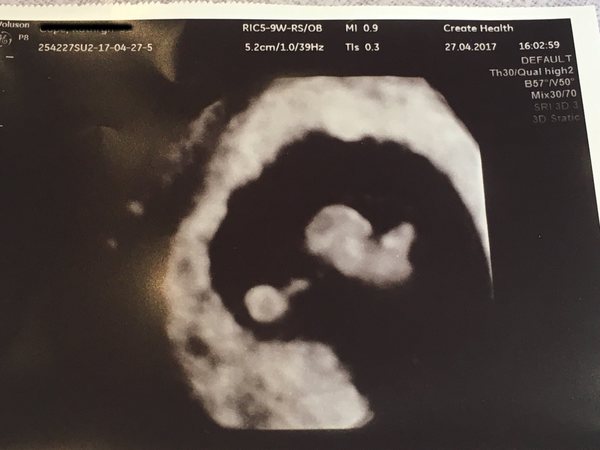

BirdBrain85 · 27/04/2017 21:30

Scan went really well. Baby is measuring correct for dates at 7+4 (gestational age 7+5 today), heart rate is fantastic at 153 and the crl measurement is 12.8mm! They confirmed my due date as the 9th of December too.

Attached the scan photo for you all. Really pleased with it as you can see baby's little profile already Smile

BirdBrain85 · 27/04/2017 21:31

Lovely pic Birdbrain. Congrats Smile

Oyster Thank you Smile - yes it was internal. That scan is 3d I think, the 2d one I have isn't so clear but still cute! Hope all goes well with yours.

Wow bird that's amazing. My scan at around 6 and a half weeks was a tiny bean shape. I can't believe how quickly they change. Can't WAIT for 12 week scan